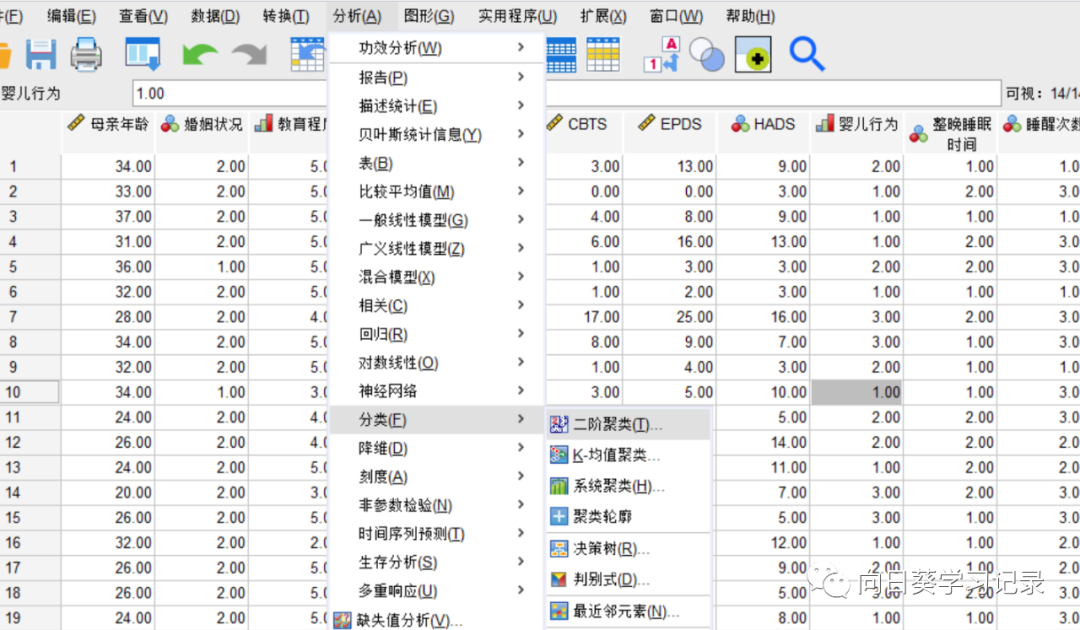

分析~聚类~k均值聚类,在保存中选择保存聚类成员,在选项中选择AVONA表和初始聚类中心,SPSS默认迭代次数为10,在迭代中修改为100。默认收敛准则为0,意味前后两个如果各点到聚类中心的之差为0,则达到收敛标准,收敛停止

将HADS选入个案标注依据,将标准化后的数值选入到变量框内,意思为根据变量(母亲年龄、CBTS、妊娠时间、EPDS)将HADS进行分类

初始聚类个数为2,在方法的左侧可以修改需要聚类的个数

(3)两步聚类

分析~分类~二阶聚类

将一些分类变量和定量变量选入到相应的方框中,测量距离选择对数似然,若只有连续变量,则可以选择欧式

聚类数目默认最大15,聚类准则为BIC

点击选项,由于SPSS默认对所有的数值变量进行标准化,因此若已进行标准化则需将待标准化计数放回到假定标准化计数内,若未进行标准化则无需进行改动